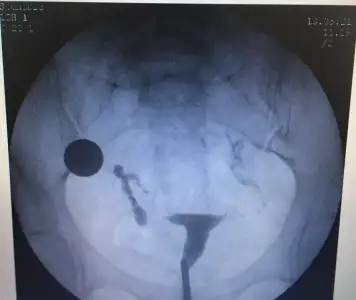

Ben bugün hsg sonucumu başka bir doktora gittim gösterdim. Bu film sağlıklı çekilmemiş, kaldı ki görüntüden de kesin tüplerin tıkalı olduğu falan anlaşılmıyor dedi. Tekrar hsg çektiricemya cevat hocada onu söyledim. İstiyosan çektir ama ben en azından 1 ay beklemeni tavsiye ederim yumurtalar radyasyona maruz kalıyor üst üste yaptırma dedi. O yüzden ben de Temmuz adetimden sonra gitme kararı aldım.

bu arada alttan ultroson yaptı hem sağdan hem soldan yumurtlamışsın dedi. Oluyor mu öyle sırayla değil mi dedim yoo dedi ben bilmiyodum

gebelik beklentim yok bu Aydan ama yumurta sayın iyi diyip üstüne 2 taraftan yumurtlamışsın diyince mutlu oldum yine de